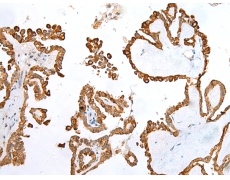

IHC positive control: |

Human thyroid cancer |